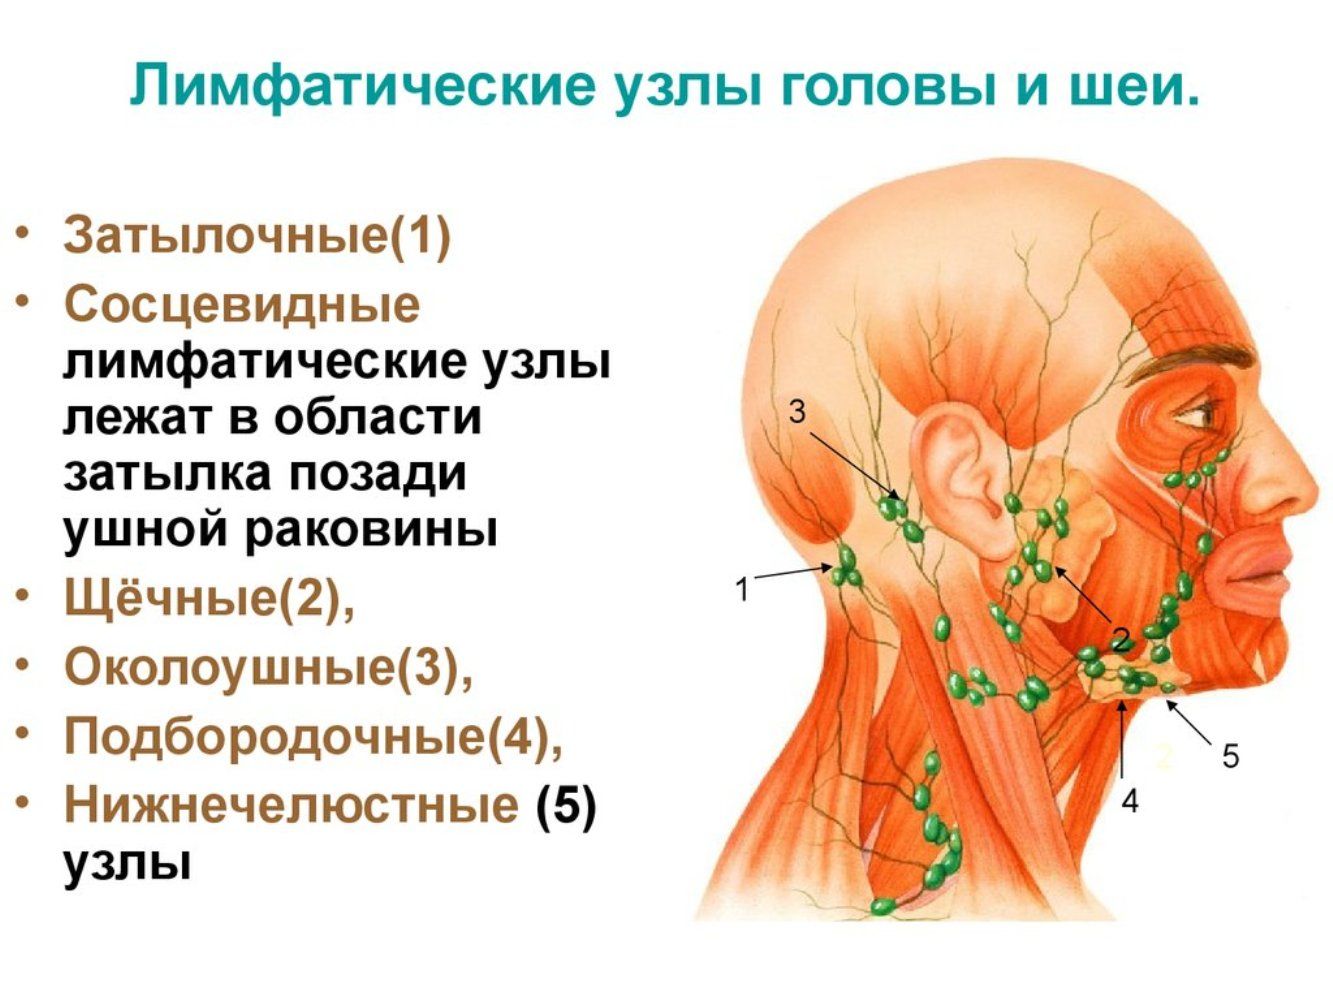

Изображения и схемы: как выглядит лимфа